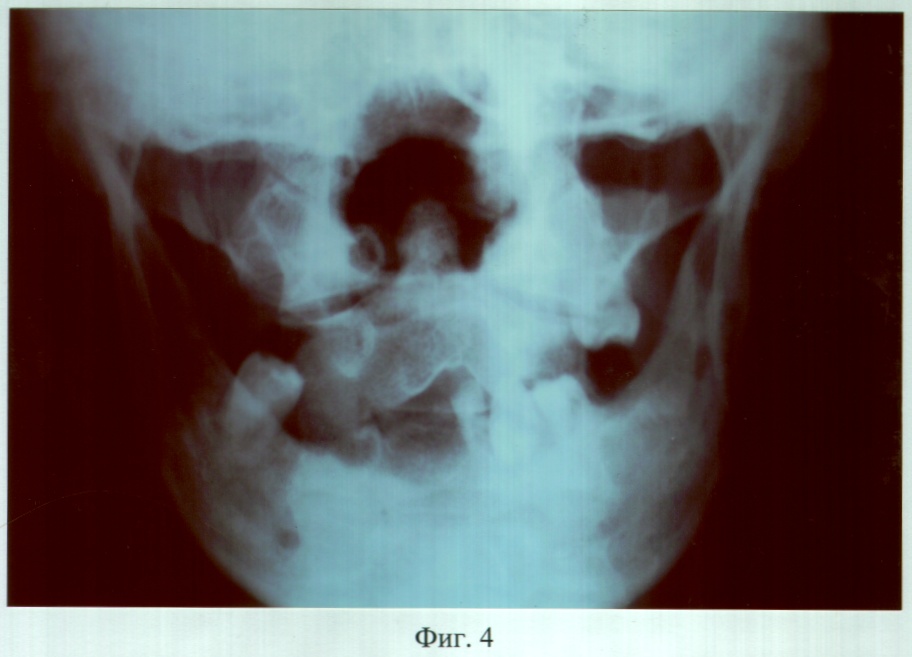

На фиг.4 – рентгенограмма больного М. до ортопедического лечения (прямая проекция).

Объективно: нарушение конфигурации лица за счет правосторонней рубцовой деформации и западения мягких тканей верхней и нижней губы, крыла носа. В проекции отсутствующих 18, 17, 16, 15, 14, 13, 12, 11; 46, 45, 44, 43, 42, 41, 31 зубов определялись аркообразные дефекты альвеолярных отростков. Ротовая полость сообщалась с носовой и носоглоткой посредством дефекта переднего и заднего отделов твердого и отсутствия мягкого неба, с сохранением 1/2 части небного отростка левой верхней челюсти. Слизистая оболочка преддверия, собственно ротовой полости, покрывающая костный изъян и ткани языка, рубцово изменены. Зубная формула: 22, 28, 32, 33, 34, 35, 47.

DS: Травматический дефект (субтотальный твердого, тотальный мягкого неба, аркообразные альвеолярного отростка правой верхней, альвеолярной части нижней челюстей в проекции отсутствующих 18, 17, 16, 15, 14, 13, 12, 11, 31, 41, 42, 43, 44, 45, 46 зубов), рубцовая деформация мягких тканей ротовой полости. Частичная вторичная верхнечелюстная и нижнечелюстная адентия II класса по Кенеди.